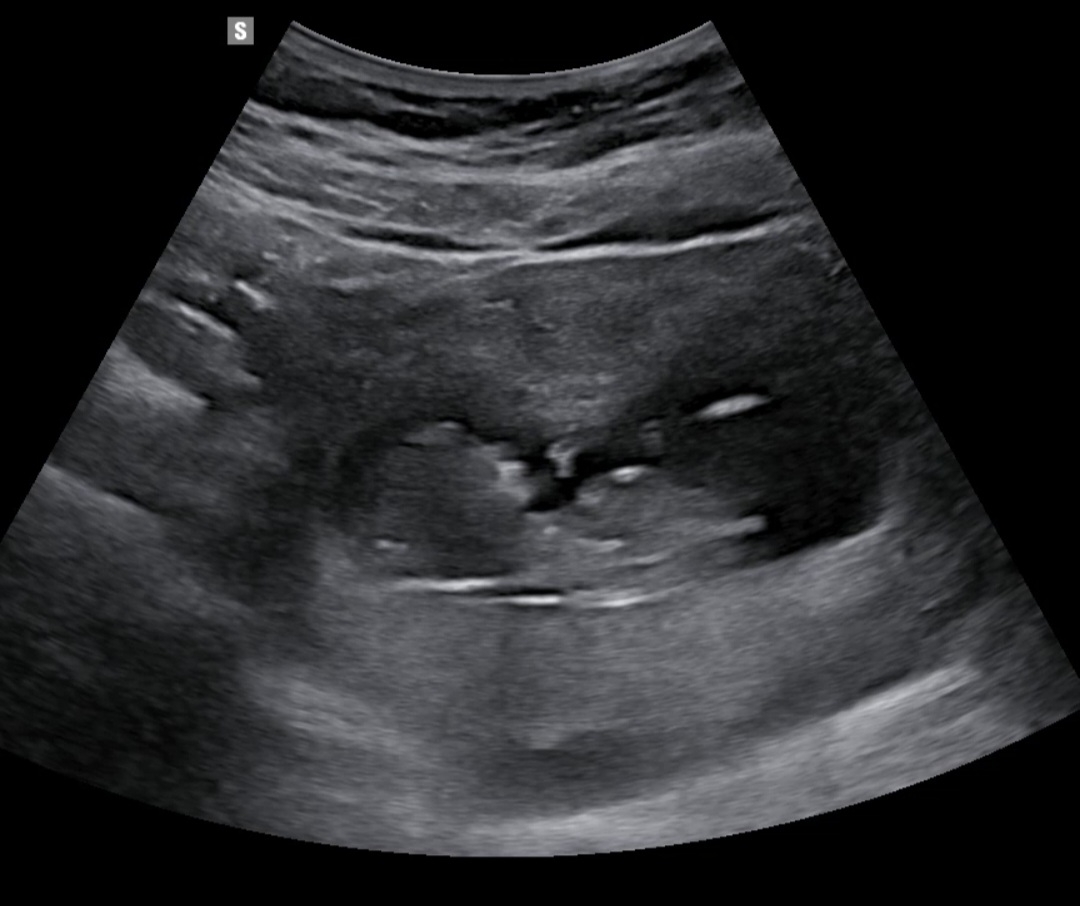

각도법 성별 참견해주세요~~!!

고수님들~ 아들 같나요?? 딸 같나요??

딸같아용